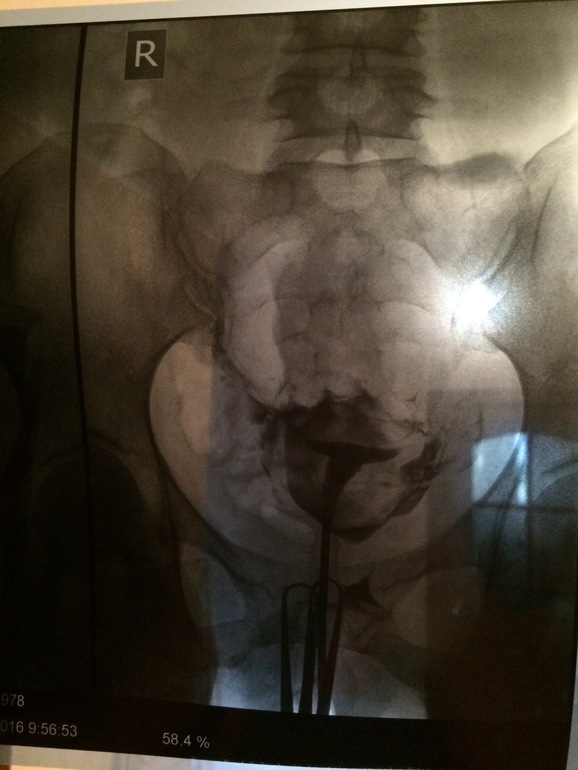

Девочки, прошла Гсг сегодня! Трубы проходимы ура! На снимке непонятно где яичники и трубы, может кто разбирается?) теперь о самой процедуре: все заняло минут 5-7. Больно немного было катетер вводить, но секунд 5 острая боль, и потом когда контраст вводили тоже сильная ноющая боль, я поойкала, но терпимо, потом снимок и сказали щас ещё введём лечебную дозу, чтобы все промыть, ещё распирающая боль, опять поойкала и снова снимок, боль именно когда вводили, видимо от напора, когда выходили делать снимок, боль сразу же проходила, щас немного тянет живот как перед м. Вообщем все более менее терпимо.

вот и прекрасно))) в снимках тока врачи разбираются. нормальные трубы и яичники нормальные у тебя, есть же О.